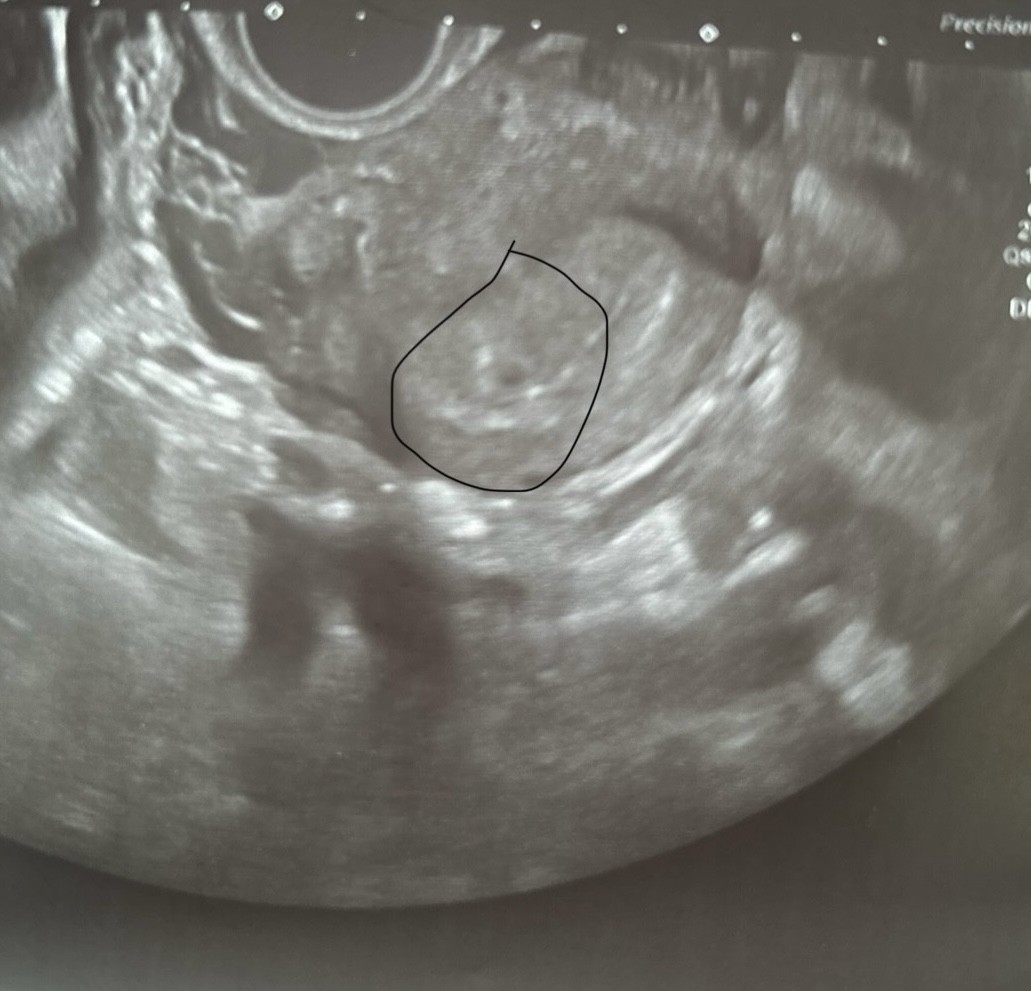

Cześć dziewczyny. Przy jakiej becie widziałyście dobrze widoczny pęcherzyk? Dzisiaj bylam na wizycie i ledwo widoczna kropka znaleziona po dłuższych poszukiwaniach, beta z tego samego dnia 1900. Miała któraś z was tak? Dobrze się skończyło? Przyrosty mam dobre, na początku to całkiem były po 600% teraz już na poziomie 170-300%. Wstawiam zdjęcie owego pęcherzyka.

• IMG_0360.jpeg

IMG_0360.jpeg

138,8 KB · Wyświetleń: 746